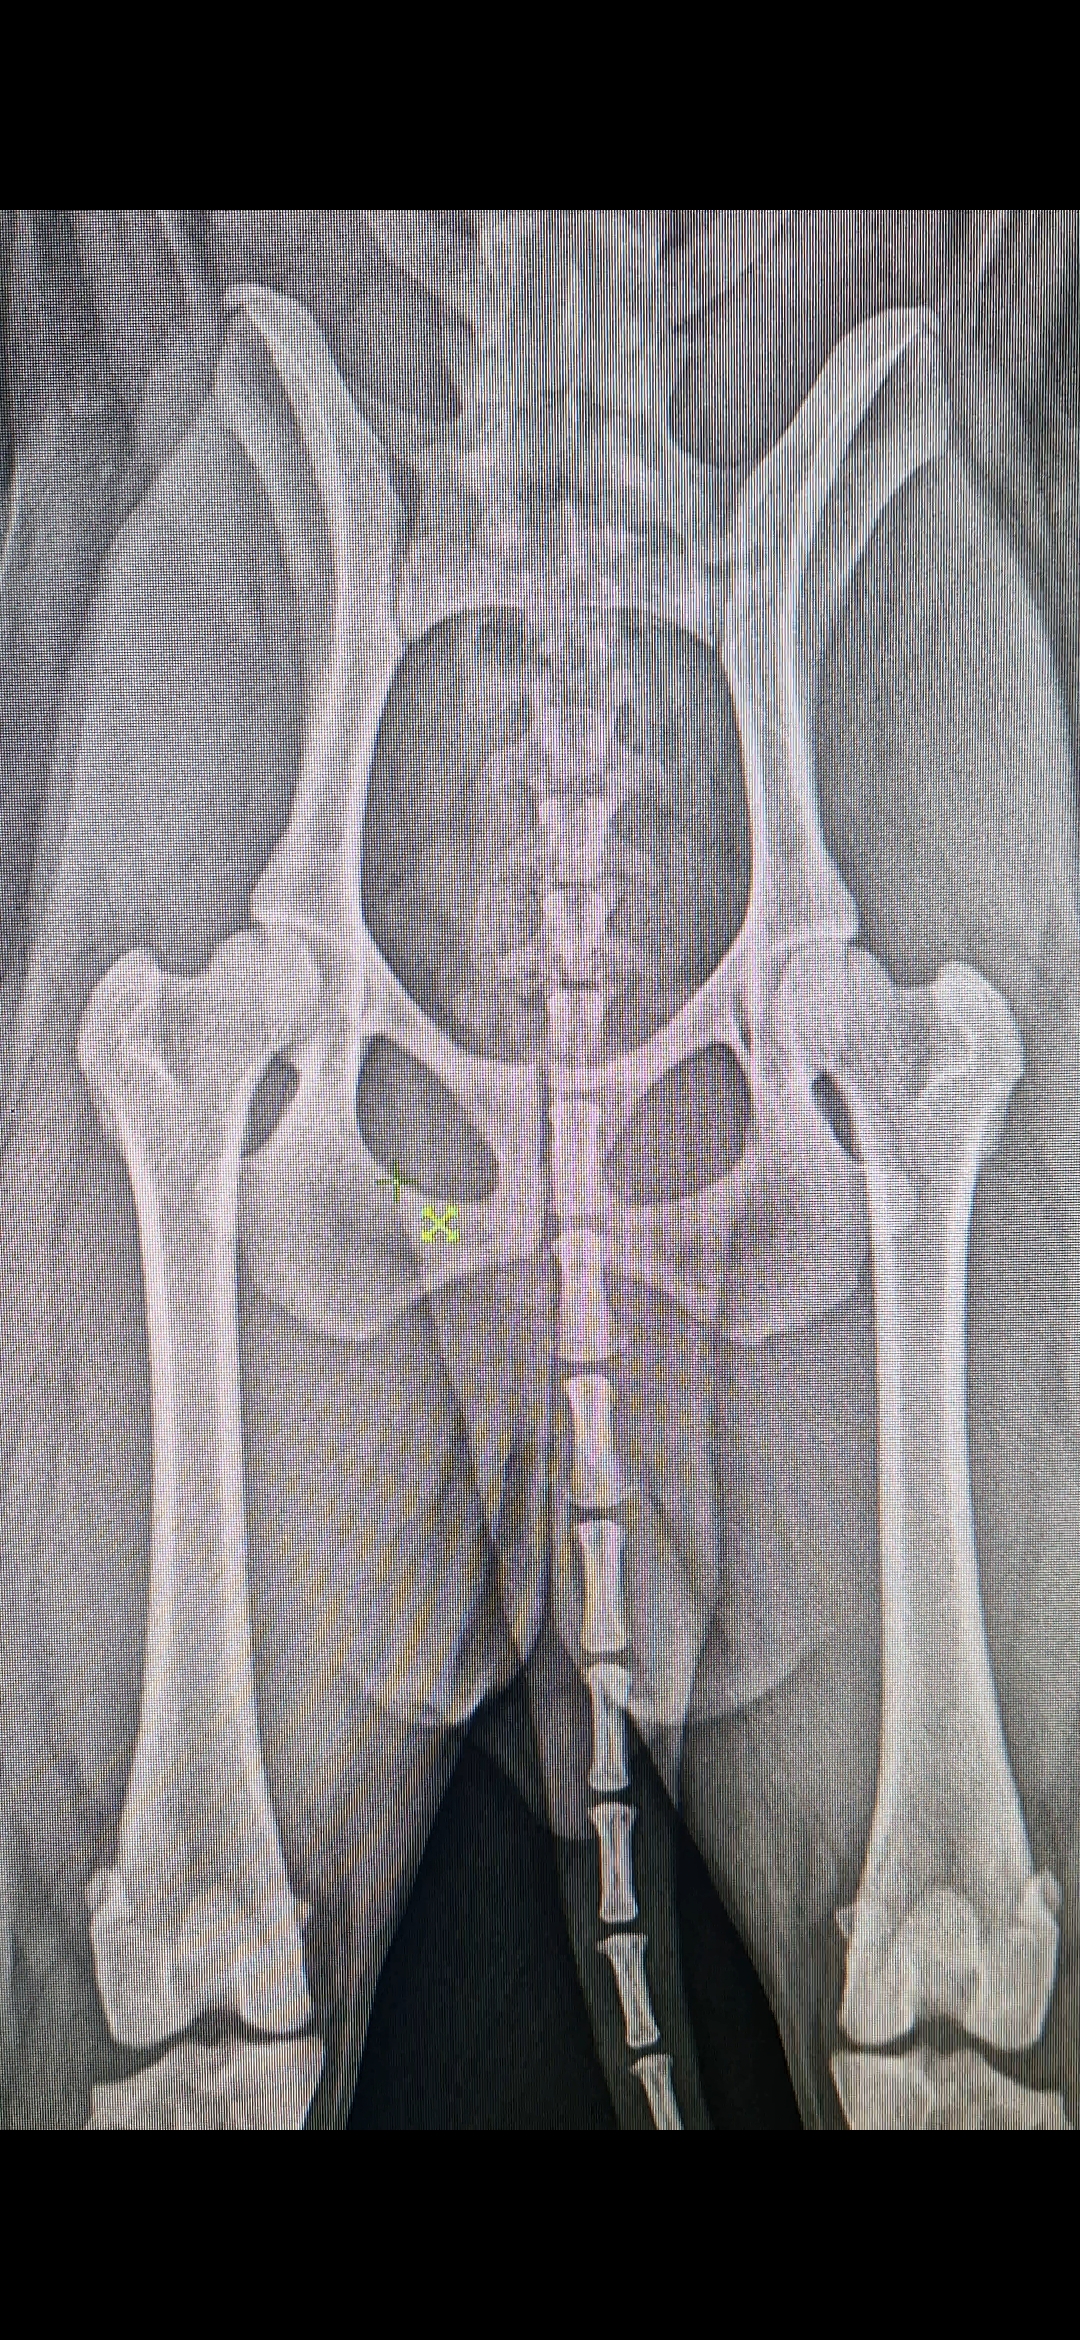

Comme la dysplasie de la Hanche est une maladie héréditaire, il est très important de savoir si un animal est porteur ou pas de cette maladie avant de le faire se reproduire. En effet cette maladie peut être sournoise et silencieuse jusqu’à ce que l’arthrose s’installe. Donc pendant toute la vie de l’animal, jusqu’à l’age « sénior », il ne présentera aucun signe de sa maladie. Le seul moyen de la mettre en évidence est la radiographie. Cette examen est réalisé à partir de l’âge de 1 ans selon un protocole très stricte.

Cet examen radiographique est réalisé sous anesthésie générale afin que l’animal soit détendu un maximum pour permettre de le placer dans la position adéquate. Dans le cadre du dépistage de la dysplasie, les clichés radiographiques sont envoyés à un juge officiel qui va les examiner. Lorsque la radiographie est réalisée dans de bonnes conditions, il pourra apprécier plusieurs points pour évaluer le degré de présence de la maladie. Il va évaluer le degré de coaptation de l’articulation, la rondeur de la tête du fémur, la présence de signes d’arthrose… Cet évaluation va se baser sur une observation subjective mais également et surtout des critère objectifs et chiffrés. Cet examen va conduire à l’obtention d’une note. La meilleur note étant A et la pire étant E. Cette notation permettra au éleveurs de favoriser les individus avec les meilleurs hanches.